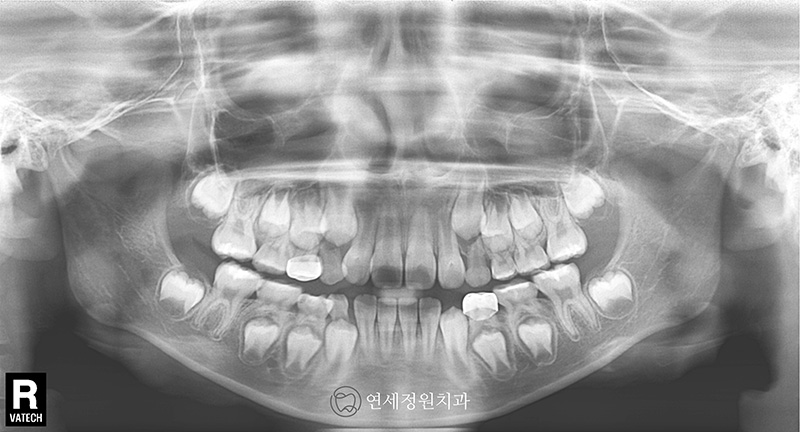

얼마 전 반가운 환자가 연세정원치과에 내원해주었습니다. 이 환자와의 인연은 9년 전 2015년 10월에 시작되었습니다. 만 7세 여자아이로 앞니가 반대로 물리는 반대교합을 주소로 처음 내원한 환자였습니다.

전치부 반대교합은 발견되는 즉시 개선해주는 것이 가장 좋습니다. 앞니가 반대로 물리는 반대교합의 개선을 위하여 페이스마스크 치료를 시작하였습니다. 보호자분과 환자의 협조도가 좋아 짧은 기간 내에 전치부 반대교합이 개선되었습니다. 반대교합이 개선된 이후 FRIII (프랑켈 장치) 로 유지를 해주었습니다.

2016년 10월